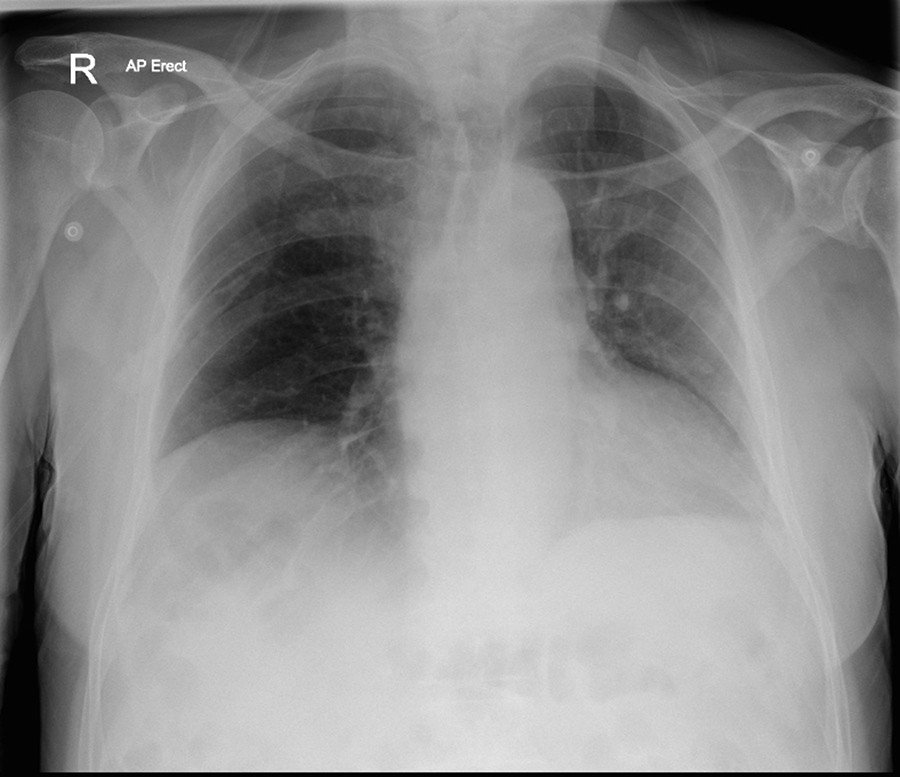

Basados en una radiografía de tórax, los médicos sospecharon que se trataba de una infección respiratoria y le recetaron antibióticos. Asimismo, consideraron que el problema de garganta era un efecto secundario de la intubación durante la operación.